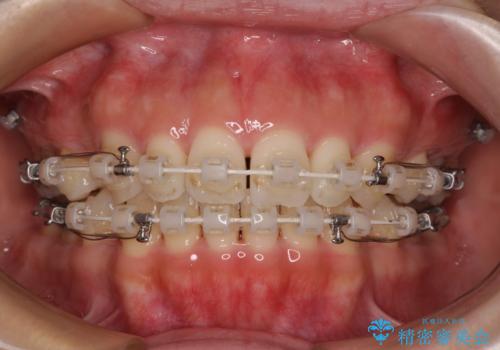

- 審美装置

- 1年8ヶ月

- 10-30回

舌の突出癖を改善するためのトレーニングをしっかりと行っていただいたことで、比較的スムーズに治療を進めることができました。

口元の突出感もしっかりと改善することができました。